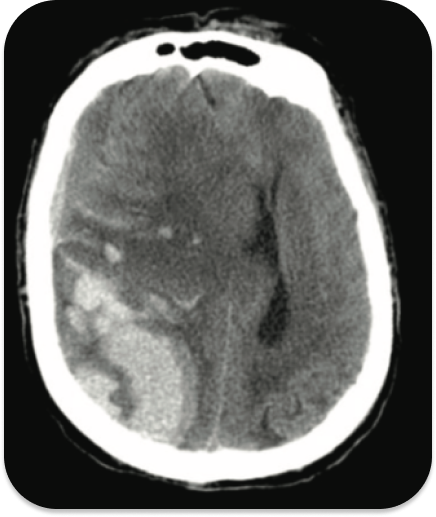

Температура 36,7 °C , кровяное давление 170/96 мм рт. ст., пульс 50 уд/мин, дыхание 10 ДД/мин. Пульсоксиметрия показывает 98% на искусственной вентиляции легких с 50% кислорода. При осмотре пациент находится в коматозном состоянии, мышечная ригидность разгибателей верхних и нижних конечностей .Неконтрастная компьютерная томография головы показана на изображении ниже:

У этого пациента, получившего травматическую травму головы, обширное внутрипаренхиматозное кровоизлияние. Внутричерепное (например, внутрипаренхиматозное) кровоизлияние может вызвать значительный массовый эффект и повысить внутричерепное давление, что может проявляться судорогами и триадой Кушинга